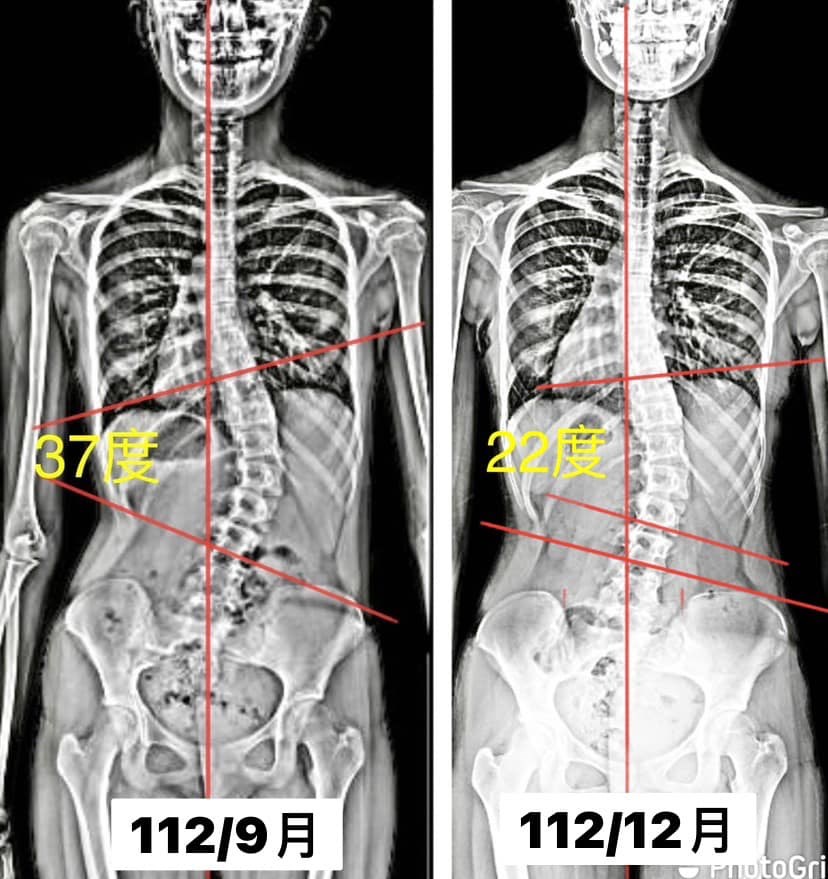

個案小軒(化名),經過三個月的 #側彎矯正訓練,整整進步了40%,從37度減少到22度

面對孩子的側彎,家長從一開始的迷惘擔心,沒有方向,但隨著課程進行,爸爸一起陪著孩子運動,媽媽一起陪著孩子進步!

側彎矯正絕對不是單方面的努力,請讓矯正從生活做起!